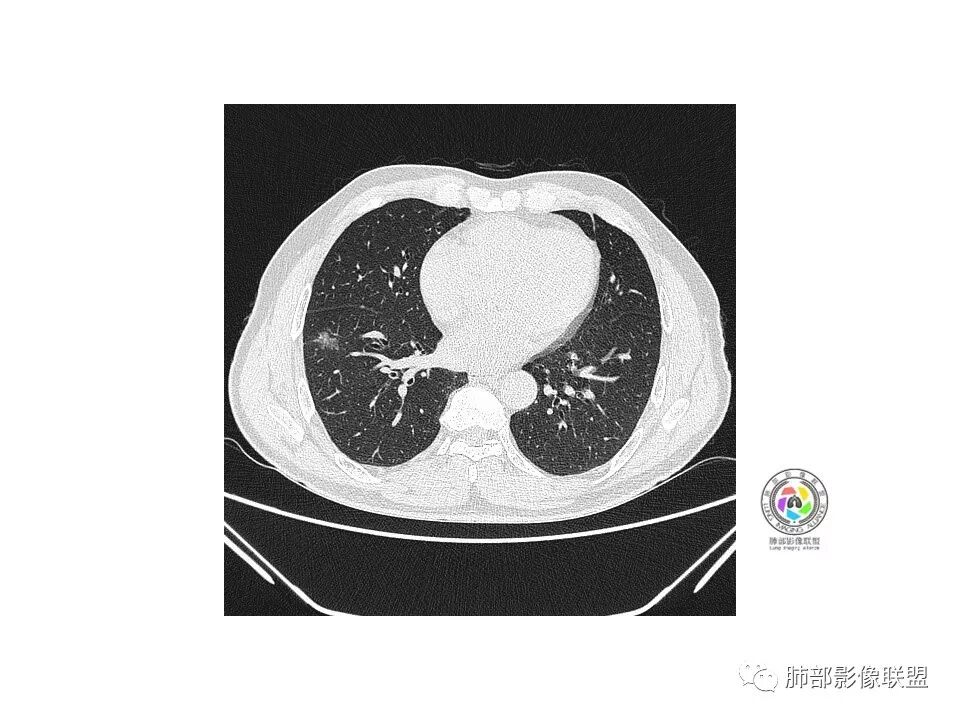

右肺下叶混合磨玻璃密度结节,有月牙铲,内可见血管,血管移动联通,常规消炎复查,还存在考虑AIS-MIA

患者老年男性,右下肺前基底段靠近胸膜侧可见一个mGGO结节,边缘清淅,可见分叶征及月牙铲,小结节病灶胸膜牵拉明显,首先考虑MIA可能性大。

右肺下叶mGGO,边缘清晰,浅分叶,内血管影增粗,见点状实性成分,小支气管牵拉扩张,考虑MIA,建议抗炎后复查。

右肺下叶前基底段mGGN,边界清晰,内部结构杂乱,见网格空泡感,月牙铲,浅分叶及胸膜牵拉,倾向MIA。

右肺下叶GGO,边缘清晰,有月牙铲,有血管进入,内部结构紊乱,胸膜牵拉,考虑MIA,常规建议抗炎治疗后复查。

右肺下叶磨玻璃结节,边界清晰,边缘有分叶及月牙铲,并可见轻度胸膜牵拉,收缩力弱,有血管移动联通征,而且病灶内血管影轻度增粗,实性成分很少,考虑AIS,可以让子弹再飞一会,或常规抗炎治疗后复查。

界清ggo,月牙铲,考虑腺癌

右肺下叶前基底段磨玻璃小结节,其内血管稍增粗,边缘见分叶、月牙铲,考虑ais,炎性结节不排

是GGN吗?边界清吗?收缩力?

边界清,收缩力强

血管如何?

血管似有增粗

有增粗,联通、移动,高度怀疑Ca,常规抗炎后复查